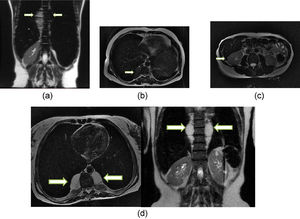

Among the EMH patients, 57.9% (n = 11) had masses that were < 5 cm in diameter, 21% (n = 4) between 5–10cm, and 21% (n = 4) >10 cm. Supplementary Table 1 details the features of the EMH patients. Four EMH images (Figures 1a-d) were selected to illustrate the radiologic characteristics of these patients. Figure 2 shows the anatomic distribution of EMH masses.

T2 fast spin echo magnetic resonance imaging (MRI) scans: A) Coronal scan of case 9, showing large soft tissue mass in the thoracic and lumbar paravertebral space (arrows); hepatosplenomegaly and marked hypo intensity of the liver and spleen, which indicates iron deposition. B) Axial scan of case 124 showing small soft tissue mass in the right thoracic paravertebral space (arrow). C) Axial scan of case 13 showing small soft tissue nodule in the hepatorenal space (arrow), presenting marked hypo intensity, indicating iron deposition. D) Axial and coronal of case 132 showing large soft tissue mass in the thoracic paravertebral space. Note the marked hypo intensity of the liver and spleen (coronal), which indicates iron deposition.